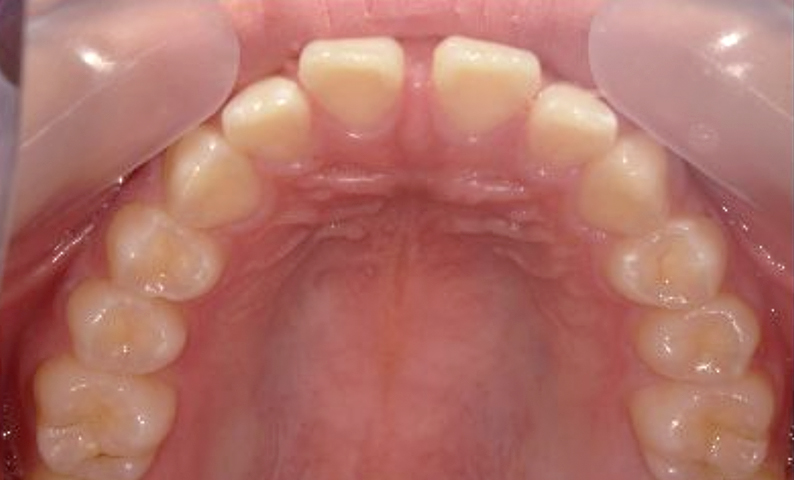

症例_004 上顎だけの部分矯正

治療期間:6ヶ月金額:27万円+税男性出っ歯上の前歯だけ

| Before | After |